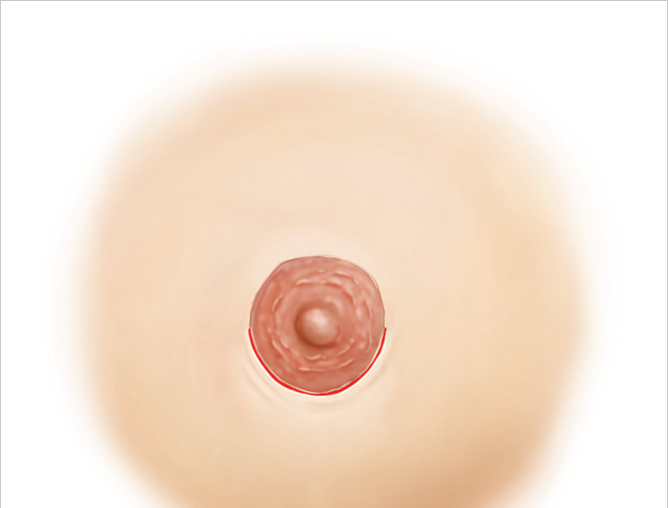

A periareolar incision should be placed directly at the junction between the outermost pigmented portion of the areola and the adjacent normal colored breast skin. Placing the incision within the areola may result in the pale scar within the pigmentation of the areola resulting in increased visibility. I usually use the inferior lower pole of the areola for such an incision from 9 to 3 o’clock position (▶Fig. 26.1).